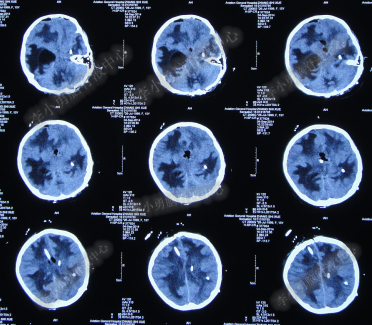

腰大池持续引流20天内,体温仍间断高热,曾3次脑脊液细菌培养均示鲍曼不动杆菌,先后使用利奈唑胺+克倍宁,利奈唑胺+克倍宁+奥硝唑,舒普深+米诺环素+来立信+氟康唑,舒普深+米诺环素+美罗培南+氟康唑,及日达仙、人免疫球蛋白提高免疫力,但颅内感染仍控制不住,期间多次头部CT检查均示脑室无明显扩张(图-7、图-8、图-9)。

图-7:2014年6月9日头部CT

图-8:2014年6月14日头部CT

图-9:2014年6月21日头部CT